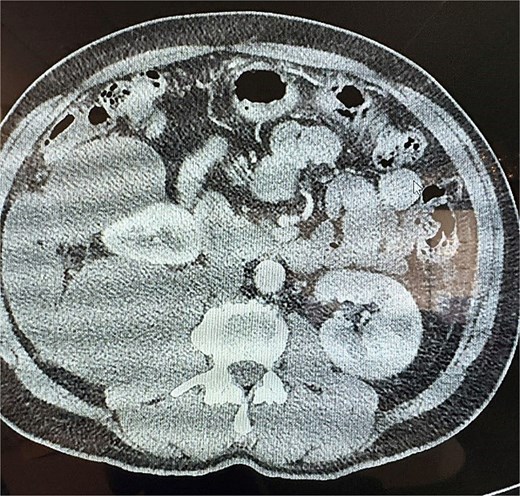

Upon further evaluation by the surgeon at follow-up, a repeat CT scan was obtained and demonstrated that the mass had grown to 28.5 cm and displayed a lobulated cystic structure with calcifications at its inferior margin. The mass was abutting the cecum and was suspected to be a mucinous neoplasm. Given the concerning size and characteristics of the tumor, surgical resection was recommended.

The surgery was performed via a midline laparotomy. Intraoperatively, the tumor was confirmed to be entirely retroperitoneal, extending from the right pelvic region to the retrohepatic space superiorly. The mass displaced the ascending colon anteriorly and the right kidney anteromedially, but maintained clear planes separating it from the kidney. Given its location and proximity to the cecum, the tumor was resected en bloc along with a right hemicolectomy to ensure complete removal as seen in Fig. 3, and a drain was left in the right paracolic gutter. Postoperatively the drain initially had a large volume output. Drain fluid and urine were sent for analysis to evaluate for urine leakage, but returned negative. The patient was ultimately discharged home on post op day 10, and the drain was eventually removed in clinic.